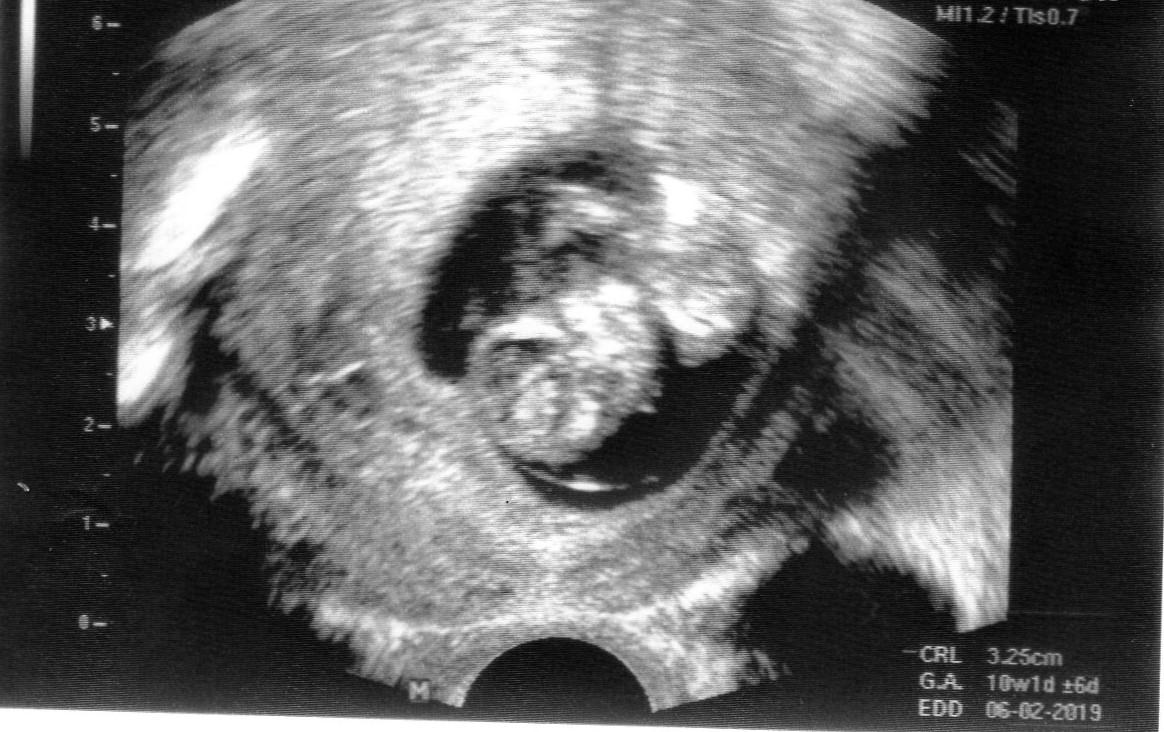

Holky já jsem včera byla na kontrole - měla bych být 11+2, a mimčo odpovídalo 10+6, takže jak to vypadalo že je o týden mladší podle minulých dvou UTZ tak už ten rozdíl je menší, všechno je prý vpořádku a v jednu chvíli bylo vidět jak se krásně protahuje - ty malinké prstíčky 🙂 Fotka je jakože hlavou dolů a ručičky má na hrudníčku - ale není to moc ostré - přijde mi že na tom monitoru to bylo vidět čistěji - byl vidět i nosík a očička hezky